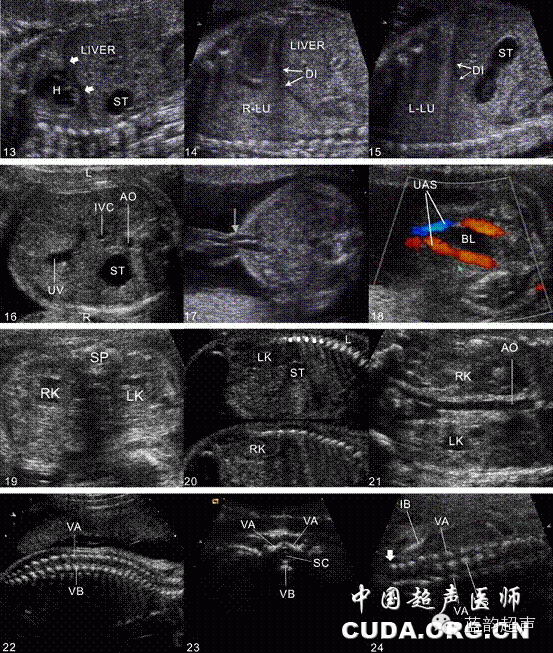

Ⅲ级产科超声检查建议存留的超声图与模式图

1、丘脑水平横切面超声图与模式图,2、侧脑室水平横切面超声图与模式图,3、小脑水平横切面超声图与模式图,4、鼻唇冠状切面超声图与模式图,5、双眼球水平横切面超声图与模式图,6、颜面部正中矢状切面超声图与模式图,7、四腔心切面超声图与模式图,8、左室流出道切面超声图与模式图,9、右室流出道切面超声图与模式图,10、三血管切面超声图与模式图,11、三血管气管切面超声图与模式图,12、测量胎心率图(多普勒或M型)超声图及模式图13、膈肌冠状切面超声图与模式图,14、右侧膈肌矢状切面超声图与模式图,15、左侧膈肌矢状切面超声图与模式图,16、上腹部横切面超声图与模式图,17、脐带腹壁入口腹部横切面超声图与模式图,18、脐动脉水平膀胱横切面超声图与模式图,19、双肾横切面超声图与模式图,20、左肾及右肾矢状切面超声图与模式图,21、双肾冠状切面超声图及模式图,22、脊柱矢状切面超声图及模式图,23、脊柱横切面超声图及模式图,24、脊柱冠状切面超声图及模式图25、肩胛骨水平横切面超声图及模式图,26、肱骨长轴切面超声图及模式图,27、尺桡骨长轴切面,28、尺桡骨短轴切面超声图及模式图,29、骼骨水平横切面超声图及模式图,30、股骨长轴切面超声图及模式图,31、胫腓骨长轴切面超声图及模式图,32、胫腓骨短轴切面超声图及模式图,33、孕妇宫颈内口矢状切面超声图及模式图,34、脐带胎盘入口切面超声图及模式图,35、胎盘厚度测量超声图及模式图,6、最大羊水池切面超声图及模式图